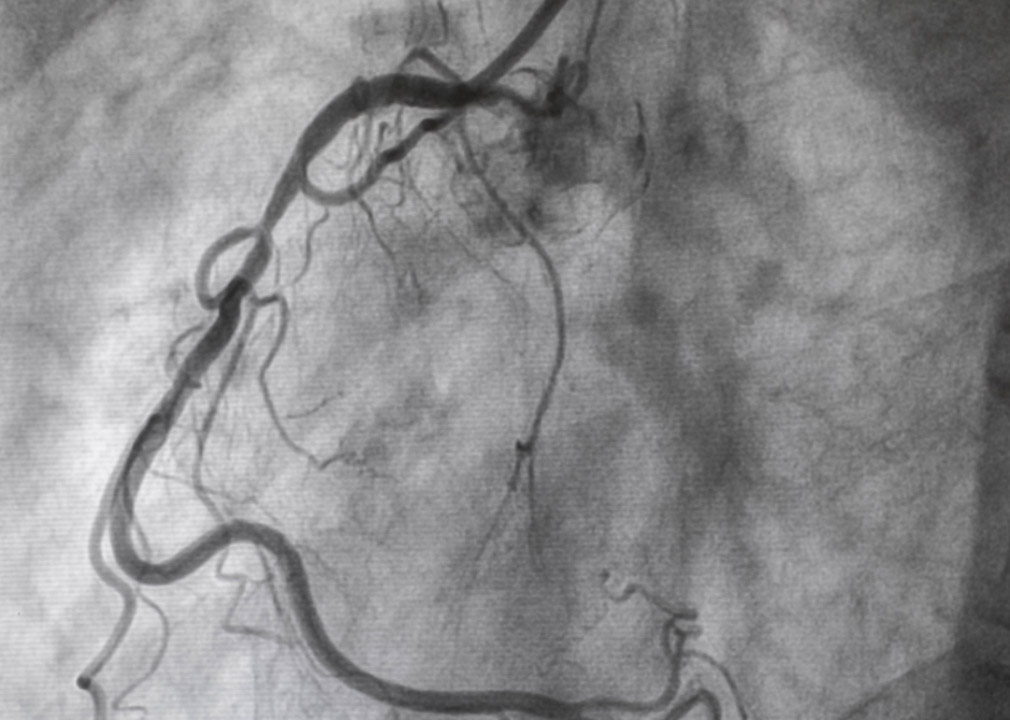

1977: World’s first heart angioplasty

The first coronary angioplasty was performed in September 1977 in Zurich, Switzerland, by Dr. Andreas Gruentzig. The patient was a 38-year-old heavy smoker with unstable angina, a chronic chest pain that occurs when the heart does not get enough blood and oxygen. The non-surgical procedure used a catheter to place a stent, or small hollow tube, in an obstructed coronary artery to increase blood flow.